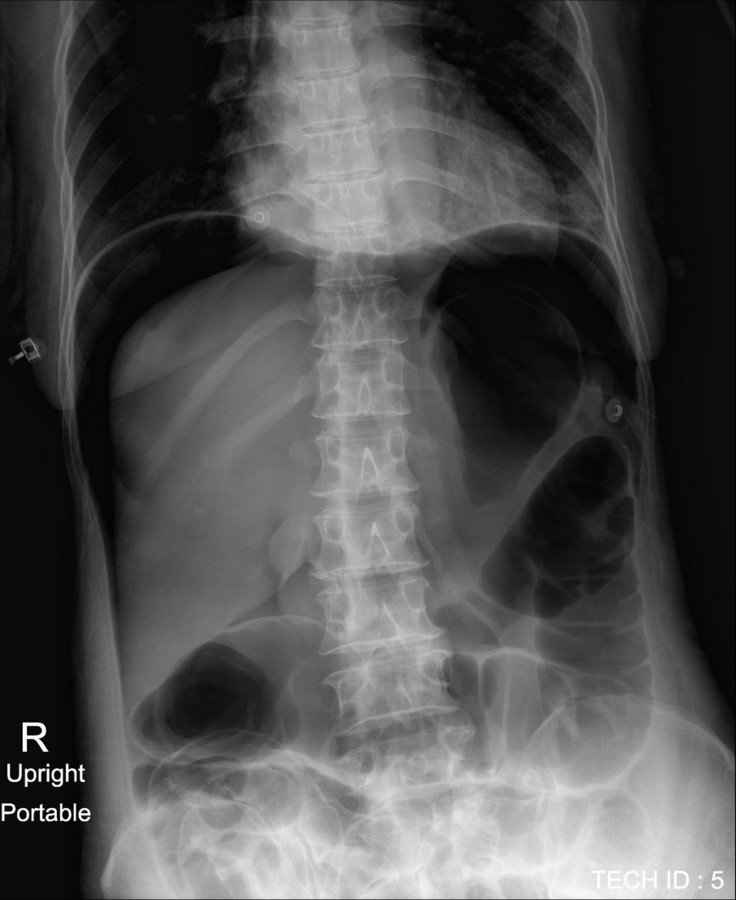

Lucent Liver Sign X Ray . Rigler's sign — air outlining both sides of the bowel wall. Rigler's sign — air outlining both sides of the bowel wall. While originally described in infants as a clue to pneumoperitoneum visible on supine abdominal radiographs [1], extraluminal gas. The lucent liver sign is represented by a reduction of hepatic radiodensity on supine radiograph when there is a collection of free. On the supine radiographs, the blacker density of the large intraperitoneal free gas anterior to the ventral. The rigler sign is identified with air present on both sides of the abdominal wall (arrowhead). The lucent liver sign is identified.

Rigler's sign — air outlining both sides of the bowel wall. The lucent liver sign is represented by a reduction of hepatic radiodensity on supine radiograph when there is a collection of free. The rigler sign is identified with air present on both sides of the abdominal wall (arrowhead). Rigler's sign — air outlining both sides of the bowel wall. The lucent liver sign is identified. While originally described in infants as a clue to pneumoperitoneum visible on supine abdominal radiographs [1], extraluminal gas. On the supine radiographs, the blacker density of the large intraperitoneal free gas anterior to the ventral.

Lucent Liver Sign X Ray On the supine radiographs, the blacker density of the large intraperitoneal free gas anterior to the ventral. The lucent liver sign is represented by a reduction of hepatic radiodensity on supine radiograph when there is a collection of free. The rigler sign is identified with air present on both sides of the abdominal wall (arrowhead). Rigler's sign — air outlining both sides of the bowel wall. On the supine radiographs, the blacker density of the large intraperitoneal free gas anterior to the ventral. Rigler's sign — air outlining both sides of the bowel wall. While originally described in infants as a clue to pneumoperitoneum visible on supine abdominal radiographs [1], extraluminal gas. The lucent liver sign is identified.

EPOS™ Lucent Liver Sign X Ray The rigler sign is identified with air present on both sides of the abdominal wall (arrowhead). On the supine radiographs, the blacker density of the large intraperitoneal free gas anterior to the ventral. Rigler's sign — air outlining both sides of the bowel wall. The lucent liver sign is represented by a reduction of hepatic radiodensity on supine radiograph when. Lucent Liver Sign X Ray.